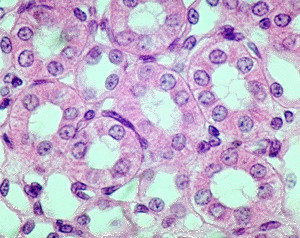

simple cuboidal

single layer of cube shaped cells; functions in tubular secretion and absorption